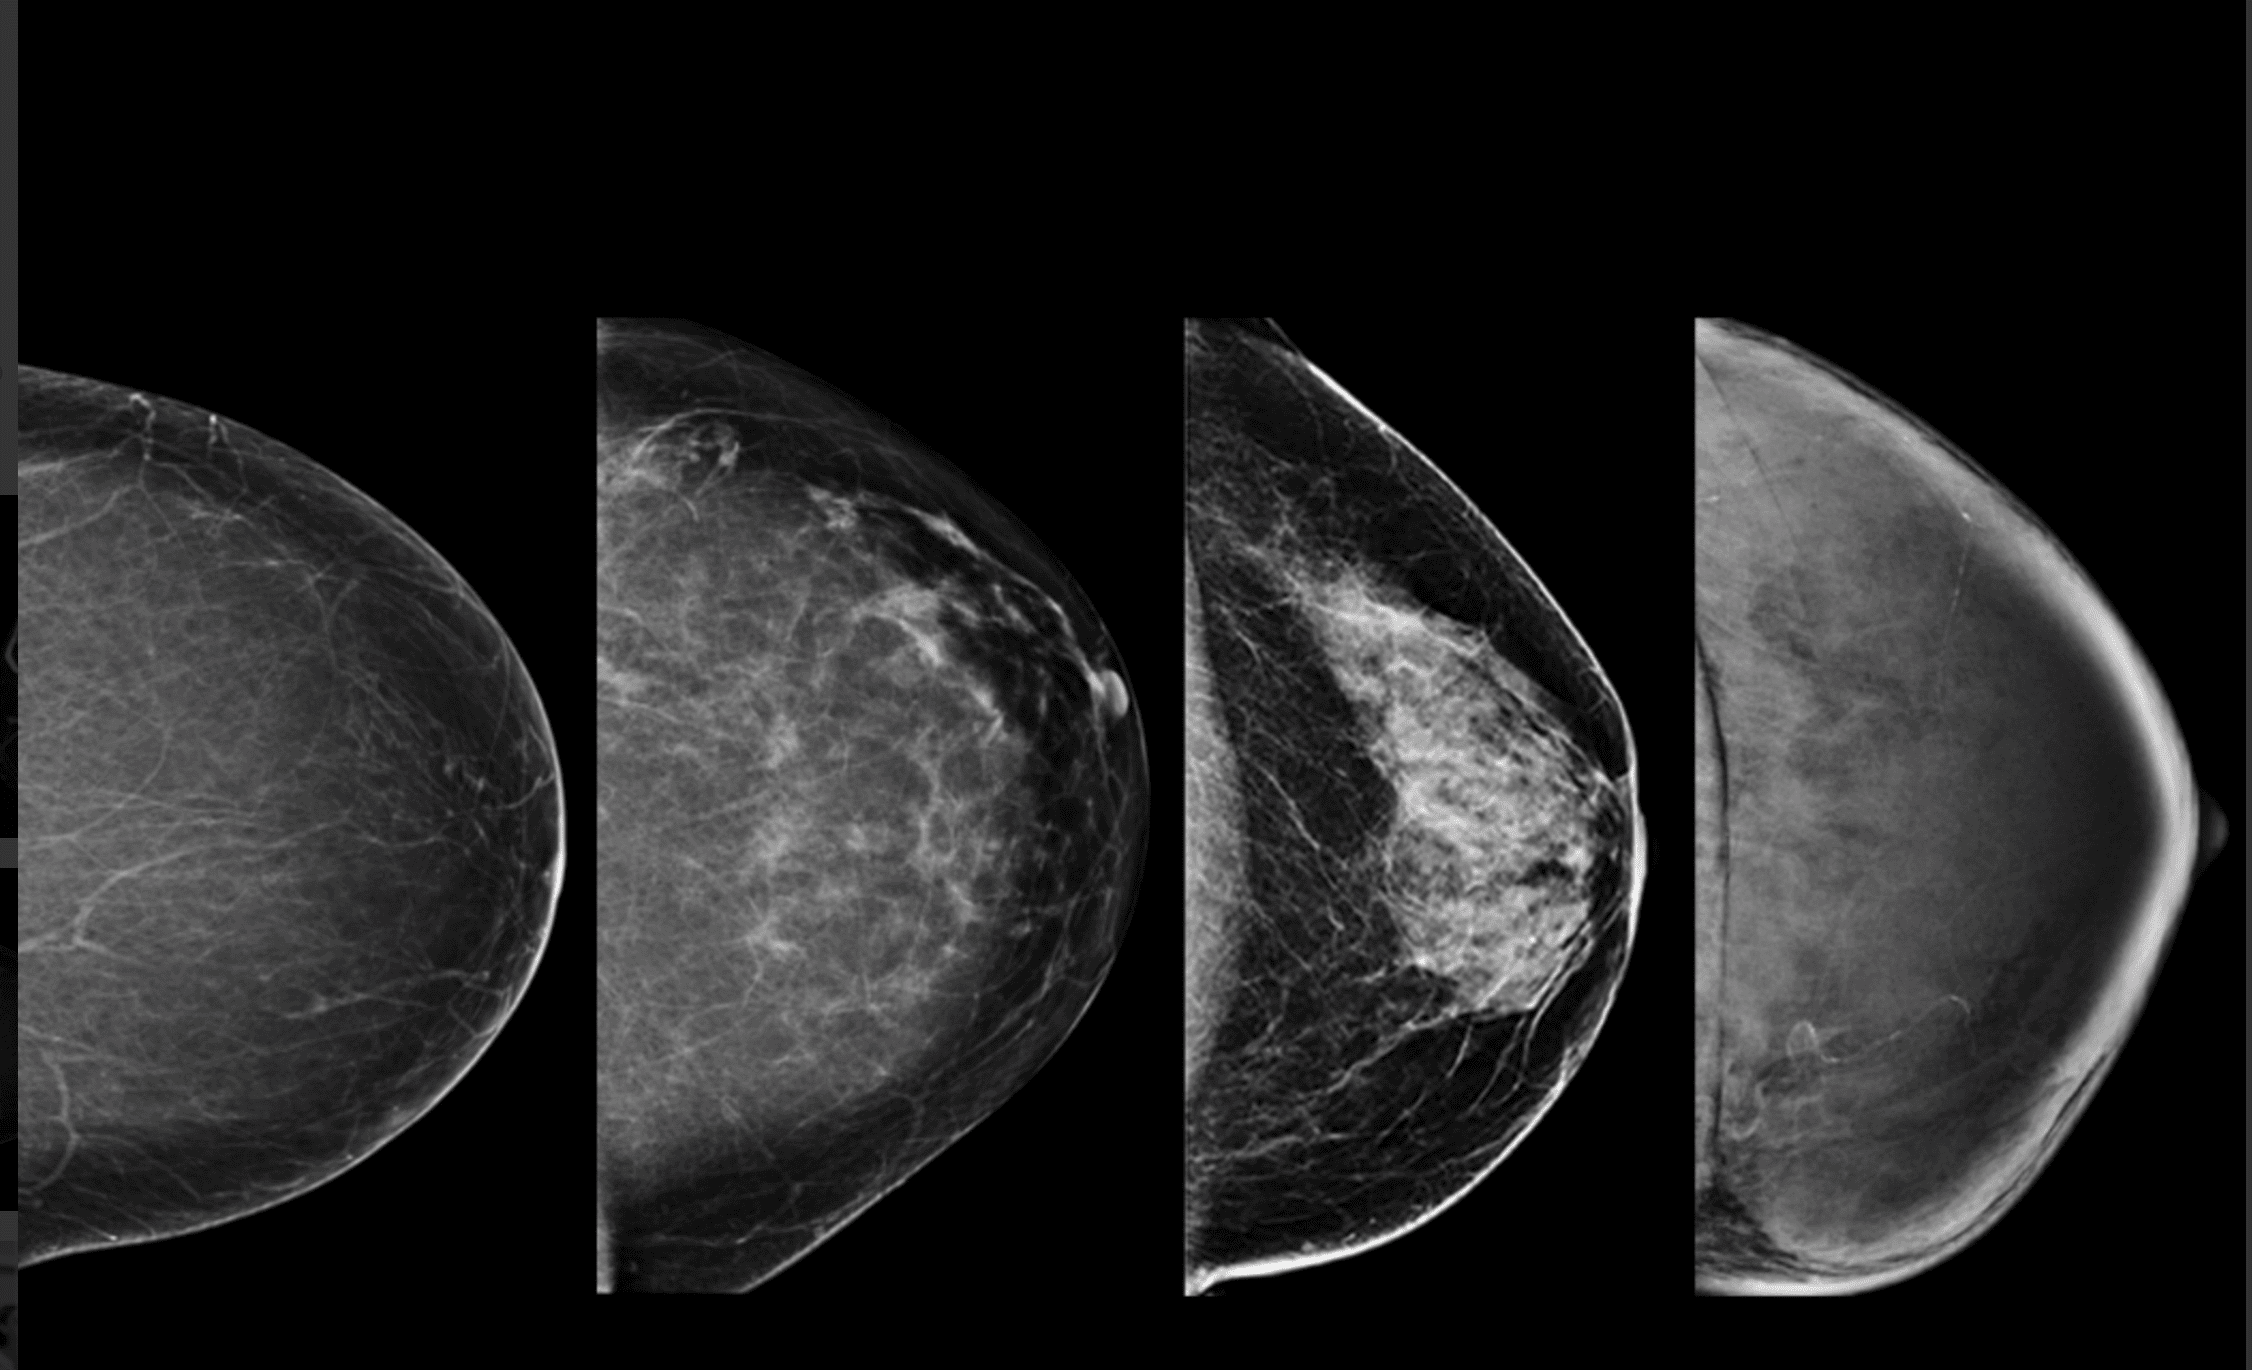

– Tessék derékig levetkőzni. Lépjen közelebb. Hajoljon kicsit le. Ne dugja a képbe a karját. Az állát fordítsa el. Most eressze le a vállát. A testével forduljon a fal felé. Dőljön előre kicsit. Fogja meg a másik kezével a rudat. Ne mozogjon. Nem jó, homályos lett, még egyszer. Ja, ezt itt el lehet forgatni. Ez egy új gép, most tanuljuk mi is. Most a másikat. Azt hittem, ez majd jobban megy. Ne rogyassza be a térdét. Húzza ki magát. Most dőljön a gép felé, és forduljon, ahogy az előbb, csak fordítva. És kicsit hajlítsa be a térdét. Öltözzön fel és üljön le kint.

– Vetkőzzön le a függöny mögött derékig. Mindent hagyjon ott. Adok lábzacskót. Adja ide a régi felvételeit. Nézzük. Ez a bal, ez a jobb. Feküdjön le. Nem, fordítva. Ez mikori? Mondtam, hogy feküdjön le. A régi CD-jét nem tudjuk beolvasni, új a gép. Ma dolgozunk vele először. Aha, ide vetíti a balt, ide a jobbat. Nem, először a bal két felvételét, aztán a jobbét együtt, összerakja. Feküdjön már le, mit nézeget. Látod, ez a kettő jön fel először. Na nézzük. Feküdjön hanyatt. Forduljon felém. Úgy, nagyon jó. Készen vagyunk. Ezt kiveszem maga alól, ezzel megtörölközhet.

kép | healthimaging.com